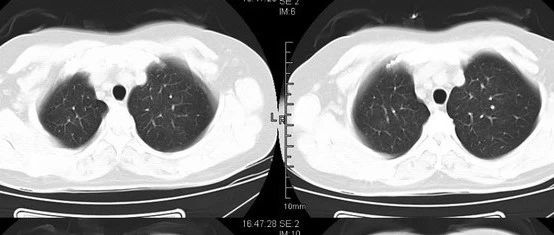

医学影像  yxyx-app  医学影像APP,打造伴随医生快速成长的影像学习社区。与影像园(Xctmr.com)一起提供最全面的影像案例库、基础(解剖、病理、影像诊断)知识、影像技术及考题等,为医生提供最佳的医学影像参考。【所属科室】呼吸科【基本资料】患者,女,42岁【主诉】反复咳嗽、咯血多年【影像图片】【讨论问题】如何诊断?【医学影像APP用户讨论】评论:...